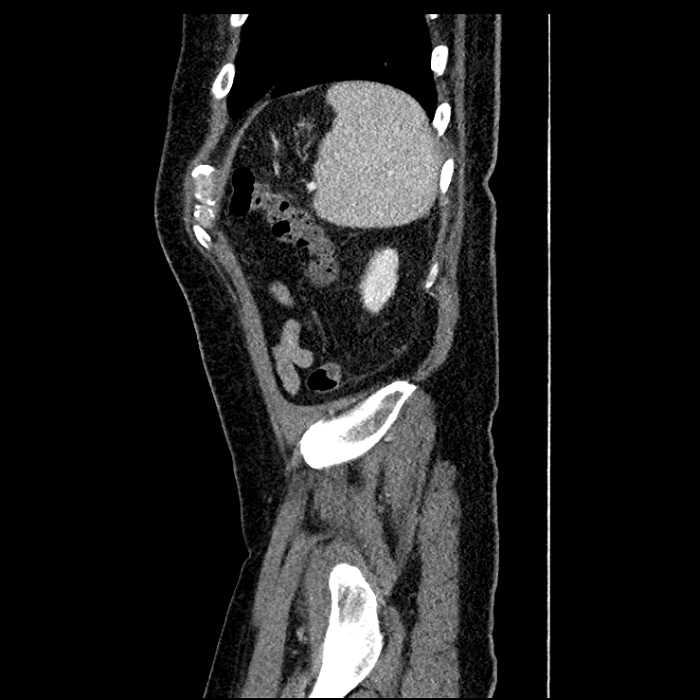

• Large fluid density structure in hepatic segments 7 and 8 measuring 10 x 7 x 7 cm with internal septation and circumferential ill-defined low density compatible with edema

• Peripherally enhancing subcapsular collections along the anterior margin of the left hepatic lobe measuring 3 x 1 cm and 2 x 1 cm

• Clearly marginated fluid density structure in segment 7 and several other scattered tiny hypodensities, which likely represent cysts

Acute sigmoid diverticulitis complicated by a small contained perforation and a large abscess in the right hepatic lobe. Additional small subcapsular abscesses along the anterior margin of the left hepatic lobe.

Additionally, loss of the normal fat plane between the peridiverticular collection and adjacent thickened loops of small bowel raises the potential for an enterocolonic fistula.

• The classic CT imaging appearance is a double target sign with internal low density surrounded by an internal enhancing rim (capsule) and a low density external rim (edema)

• Abscesses may be unilocular or multilocular

• Gas is present in a minority of cases

Hepatic abscess showing the double target sign with low density internally surrounded by a thin inner enhancing rim (red arrow) and ill-defined outer low density rim (yellow arrow). Blue arrow indicates an internal septation. Red arrows: additional smaller subcapsular abscesses. Red arrow: focal contained perforation associated with diverticulitis.